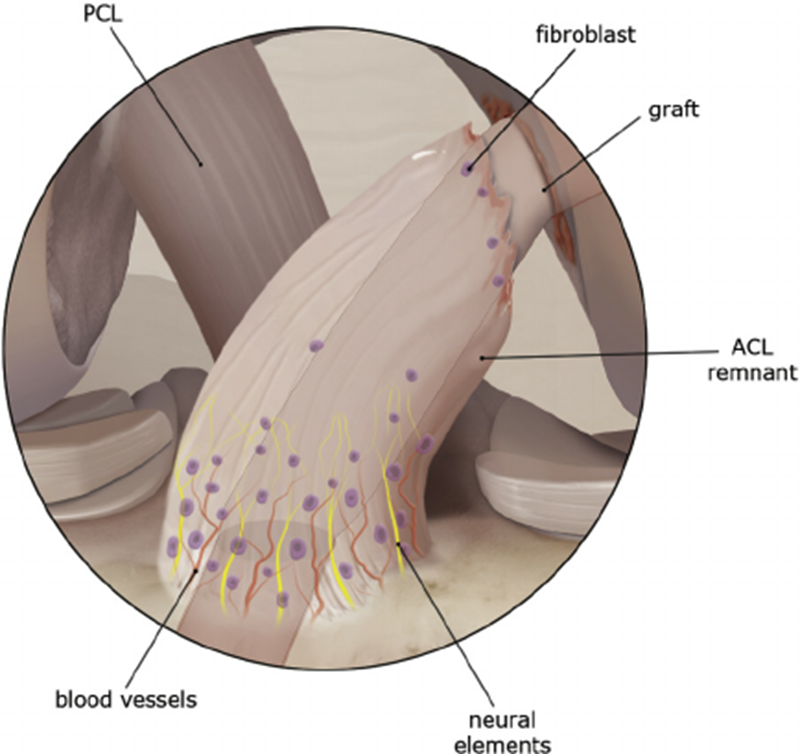

ACL无血管组织,韧带滑膜中营养血管在ACL远端、近端血管在韧带表面滑膜中形成血管丛营养韧带。

ACL除胶原外还有纤维母细胞,沿长轴分布于纤维之间,纤维母细胞主要分布在ACL胫骨端1/3前部(伸直位“生理性撞击”)。

ACL神经支配,神经纤维主要分布在ACL滑膜下和附着点部位,韧带附着点和表面存在大量Golgi样张力感受器,Ruffini小体、Pacinian小体和等机械感受器,韧带内部还存在少量机械性感受器,分布于韧带近胫骨部分,参与膝关节本体感觉传入。

Junkin等研究发现,ACL 损伤后可导致膝关节不稳定,本体感觉下降。ACL不仅是一个机械结构,也是一个本体感觉器官。

ACL保残重建,可以恢复机械稳定性,恢复本体感觉。

ACL保残重建,以韧带残余为ACL-R的位点的重要参考,贯彻“I.D.E.A.L”理念。

ACL保残重建,可以将移植物包裹住,封闭移植物与韧带之间的腔隙,避免出现关节内液体对肌腱及隧道形成的雨刷效应,能够利于愈合,防止ACL术后隧道扩大。

ACL保残重建,可以最大限度的解剖重建ACL。